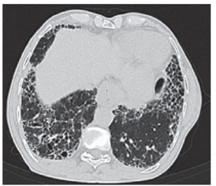

Figure 2: HRCT shows bilateral diffuse Interstitial lung disease in the form of interlobular and intralobular septal thickening predominantly in sub pleural region with focal areas of tiny honeycombing with left sided pleural effusion. Findings are in favour of idiopathic interstitial pneumonia- nonspecific interstitial pneumonia.